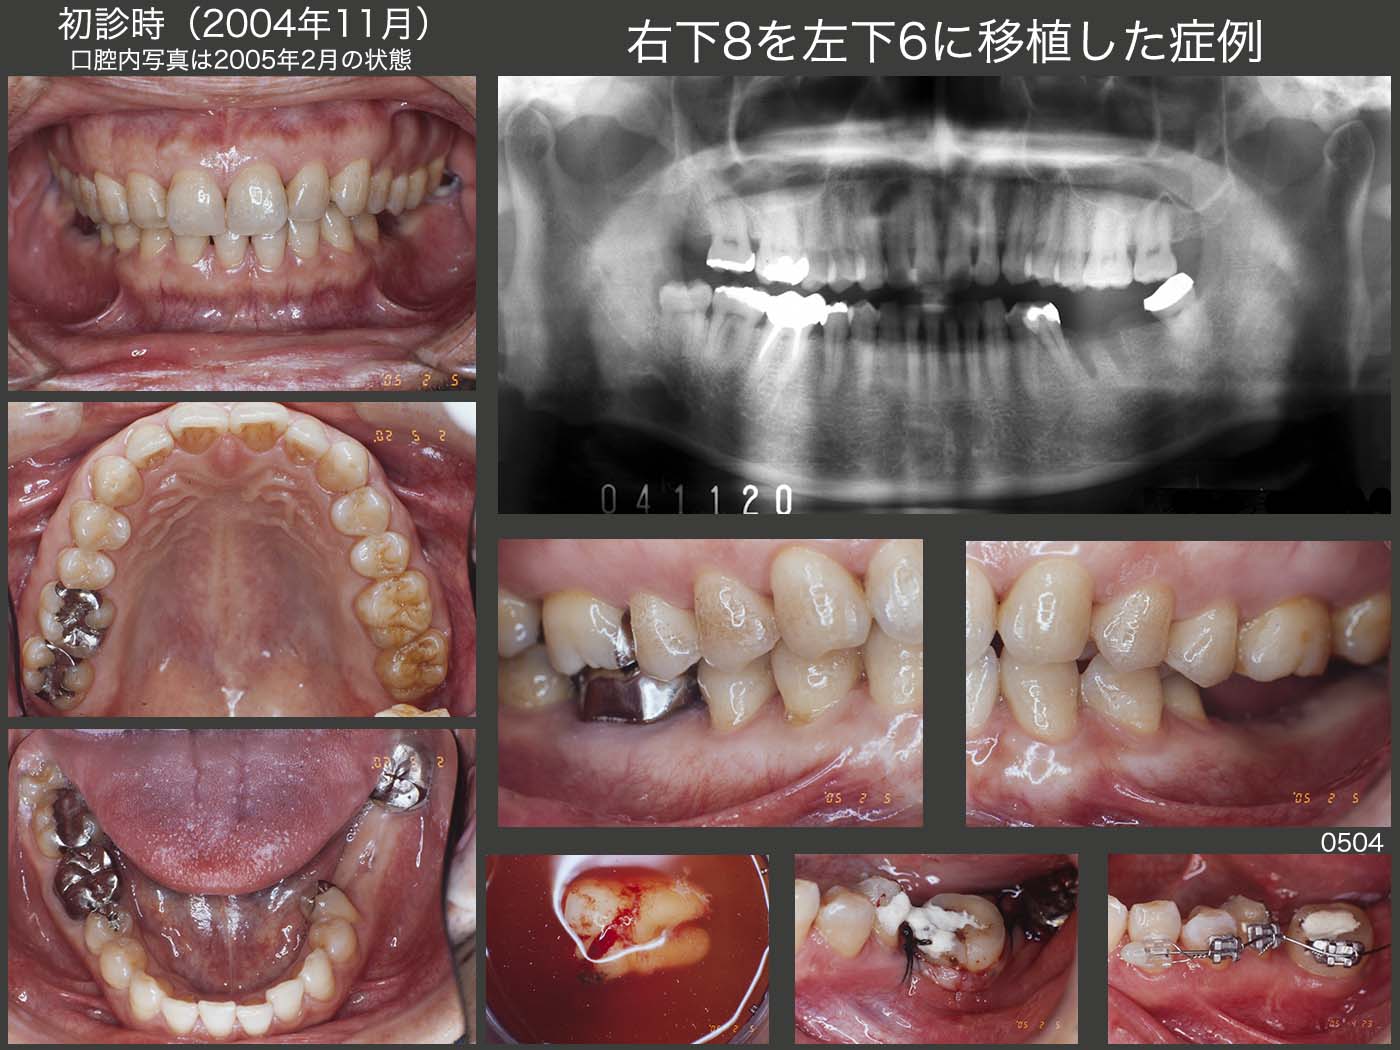

15.右下8を左下6に移植した症例

2004年11月初診,43歳男性.主訴は,左下6抜歯後の治療相談.左下⑥7⑧のブリッジが装着されていたが,左下6にヒビがはいり,先月抜去したとのこと.移植,インプラントについて本で調べたが,もっと詳しく知りたいとのことで来院.移植,インプラントそれぞれの利点・欠点を述べたが,今回患者さんは歯の移植を選択された.同時に,舌側転位した左下5のアップライトも行うことで合意した.

スライドは05年2月,歯の移植を行う直前の口腔内の状態.半埋伏の右下8の歯根膜をなるべく傷つけないで抜去することが成功への鍵である.(この時は,ドナー歯に矯正力を与えていないが)2月5日に歯の移植を行い,4月23日に左下5の歯科矯正を開始した.なおこの際,移植歯も固定源として参加させた.